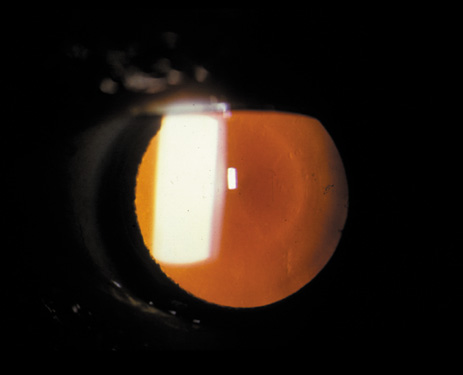

POSTERIOR SUBCAPSULAR CATARACT

The PSC is the least prevalent subtype in most population-based studies.18 These cataracts often occur in combination with nuclear or cortical cataracts in the later stages. They are easily noticed on retroillumination because they are usually located centrally, and may interfere with funduscopy (Fig. 12). In early stages, patients usually complain of subjective symptoms such as glare disability32 and difficulty focusing on near objects. This is because when the pupil constricts during accommodation, the light entering the eye becomes concentrated centrally, where the PSC is also located. This causes light scattering and interferes with the ability of the eye to focus an image on the macula. In addition, these opacities lie at or near the nodal point of the eye, further interfering with focusing of the image on the macula.

Fig. 12. PSC. Note the central location, which gives rise to severe glare disability.